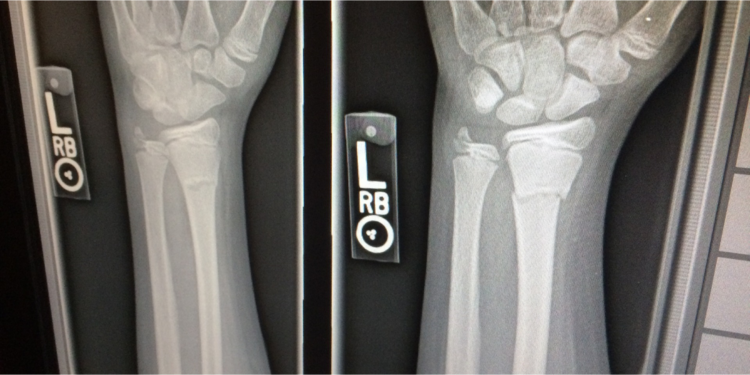

Background: In medical imaging, prior studies have demonstrated disparate AI performance by race, yet there is no known correlation for race on medical imaging that would be obvious to the human expert interpreting the images.

Findings: Standard deep learning models can be trained to predict race from medical images with high performance across multiple imaging modalities. Our findings hold under external validation conditions, as well as when models are optimized to perform clinically motivated tasks. We demonstrate this detection is not due to trivial proxies or imaging-related surrogate covariates for race, such as underlying disease distribution. Finally, we show that performance persists over all anatomical regions and frequency spectrum of the images suggesting that mitigation efforts will be challenging and demand further study.

Firstly, the performance of these models ranges from high to absurd. An AUC of 0.99 for recognising the self-reported race of a patient, which has no recognised medical imaging correlate? This is flat out nonsense.

Every radiologist I have told about these results is absolutely flabbergasted, because despite all of our expertise, none of us would have believed in a million years that x-rays and CT scans contain such strong information about racial identity. Honestly we are talking jaws dropped — we see these scans everyday and we have never noticed.

Next we tried to pin down what sort of features were being used. There was no clear anatomical localisation, no specific region of the images that contributed to the predictions. Even more interesting, no part of the image spectrum was primarily responsible either. We could get rid of all the high-frequency information, and the AI could still recognise race in fairly blurry (non-diagnostic) images. Similarly, and I think this might be the most amazing figure I have ever seen, we could get rid of the low-frequency information to the point that a human can’t even tell the image is still an x-ray, and the model can still predict racial identity just as well as with the original image!

Performance is maintained with the low pass filter to around the LPF25 level, which is quite blurry but still readable. But for the high-pass filter, the model can still recognise the racial identity of the patient well past the point that the image is just a grey box …